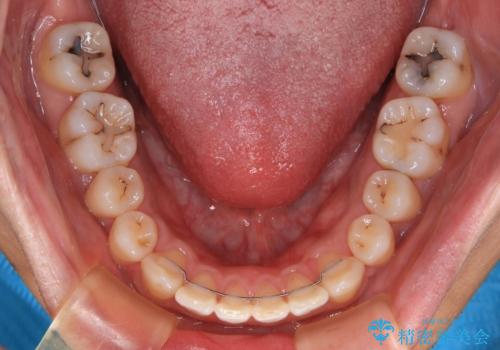

深い咬み合わせと前歯の隙間 ハーフリンガルによる矯正治療

- 咬み合わせにより上顎正中に隙間ができているとのことで来院された患者様です。

インビザラインは自己管理が煩わしく、表側のワイヤー装置は目立つので避けたいとのことで、上顎だけが裏側装置のハーフリンガルにて矯正治療を行うこととしました。